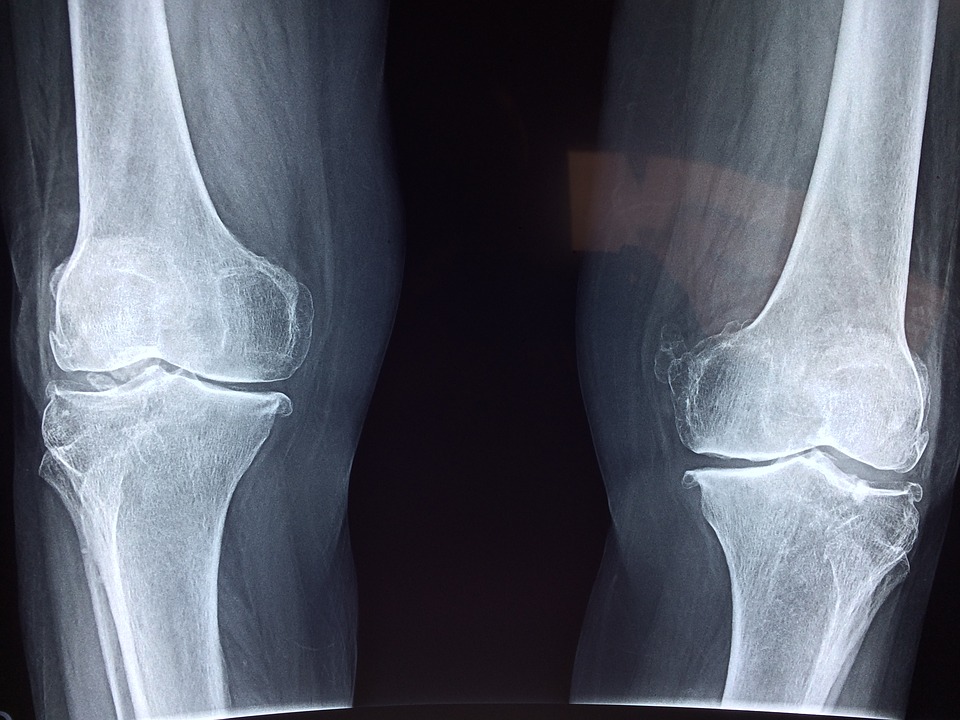

A kollagén nem más, mint egy olyan óriásmolekula, ami a szervezetünk felépítéséért felel. Nem is gondolnánk, de a kollagén hatásai jótékonyan érezhetőek a mindennapjainkban. Ha nincs elegendő belőle, akkor azt sajnos azonnal észlelni fogjuk, hiszen az ízületeink elkezdenek fájni. Szerkezetét tekintve nagyon erős, rostos, így képes csillapítani a különböző mechanikai hatásokat. 5 típusú kollagén található a szervezetünkben és mindegyiknek megvannak a szerepei. Az első típusú kollagén hatásai a bőrön vehetőek észre, hiszen ez felel a szépségért és a bőr rugalmasságáért.

A porcok épségéért a második típus felel. Ha porcerősítő terméket szeretnénk vásárolni, akkor olyan terméket kell keresni, amelyikben kifejezetten a második típus található. A harmadik típusú kollagén hatásai főleg a tüdő és a máj működésére terjednek ki, de felel az artériák egészségéért is. A negyedik a vese és a belső szervek felépítésében található, míg az ötödik főleg a haj szerkezetéért felel. Tehát bárki meg tudja határozni, hogy melyikre van szüksége.